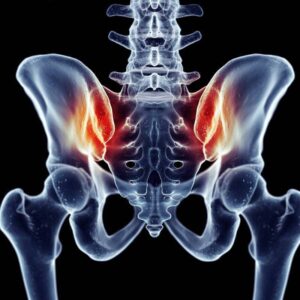

Die Orthopädie ist ein medizinisches Fachgebiet, das sich mit der Prävention, Diagnose und Behandlung von Erkrankungen und Verletzungen des Bewegungsapparates beschäftigt. Knochen, Gelenke, Muskeln, Sehnen und Bänder müssen gemeinsam funktionieren, um uns Beweglichkeit und Stabilität zu ermöglichen.

Auf unserer Seite finden Sie umfangreiche Informationen zu orthopädischen Beschwerden und Erkrankungen. Von der Arthrose über Bandscheibenvorfälle bis hin zu Kreuzbandriss und weiteren Sportverletzungen: wir geben Ihnen einen Überblick über die häufigsten orthopädischen Krankheitsbilder, wie sie behandelt werden können und inwieweit ein Bildgebungsverfahren, wie eine (z.B. MRT Knie, Rücken MRT) bei der Diagnose bei der Diagnose unterstützend wirken können.